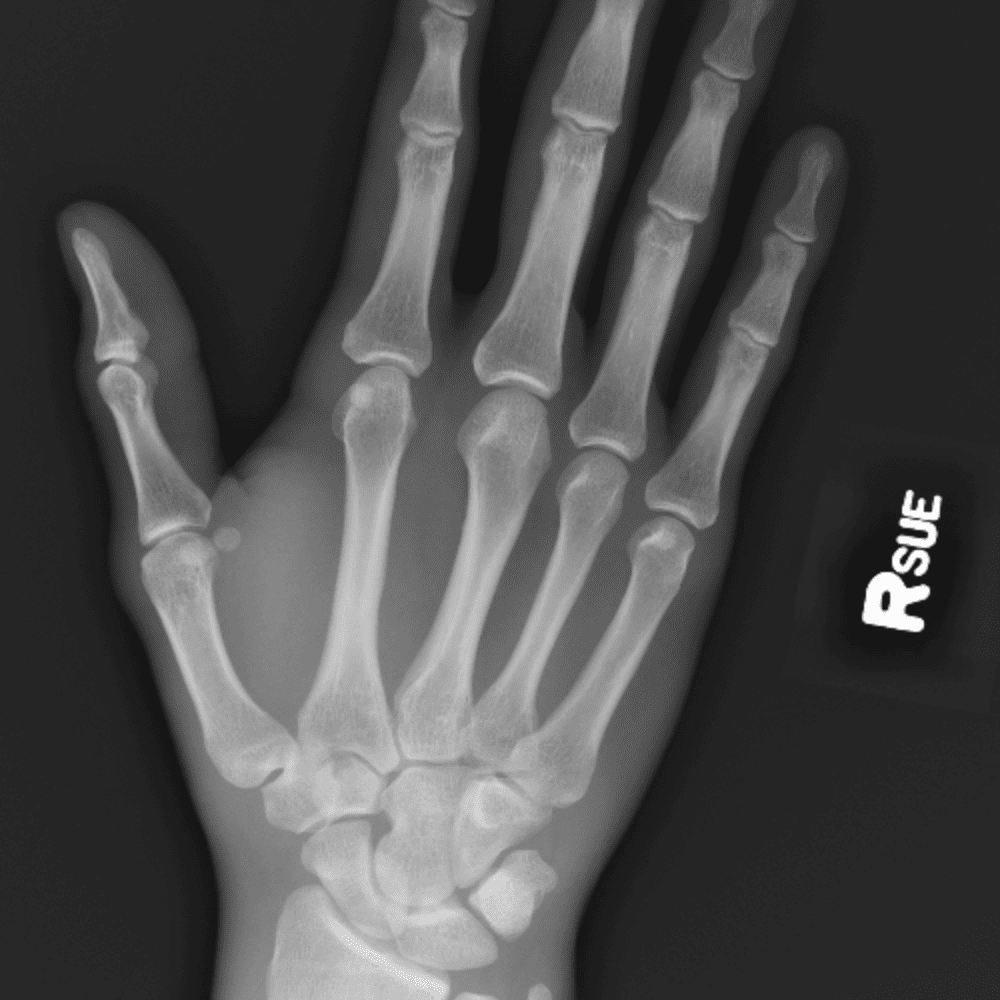

Simuliert den Dienst durch subtile oder schwierige Fälle und einige Normalbefunde.

30 Fälle